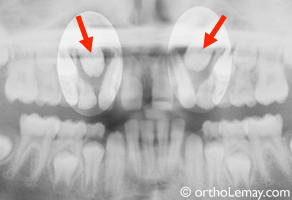

Les radiographies permettent de localiser et d’identifier la présence de dents incluses comme le montre cet exemple.

(A) Ce jeune patient se plaignait d’une “bosse au palais” (indiquées par les flèches).

(B, C) En bouche, il y a absence de la canine permanente supérieure gauche (flèche) que les parents croyaient avoir fait extraire!

(D) La radiographie confirme la présence d’une canine permanente incluse.